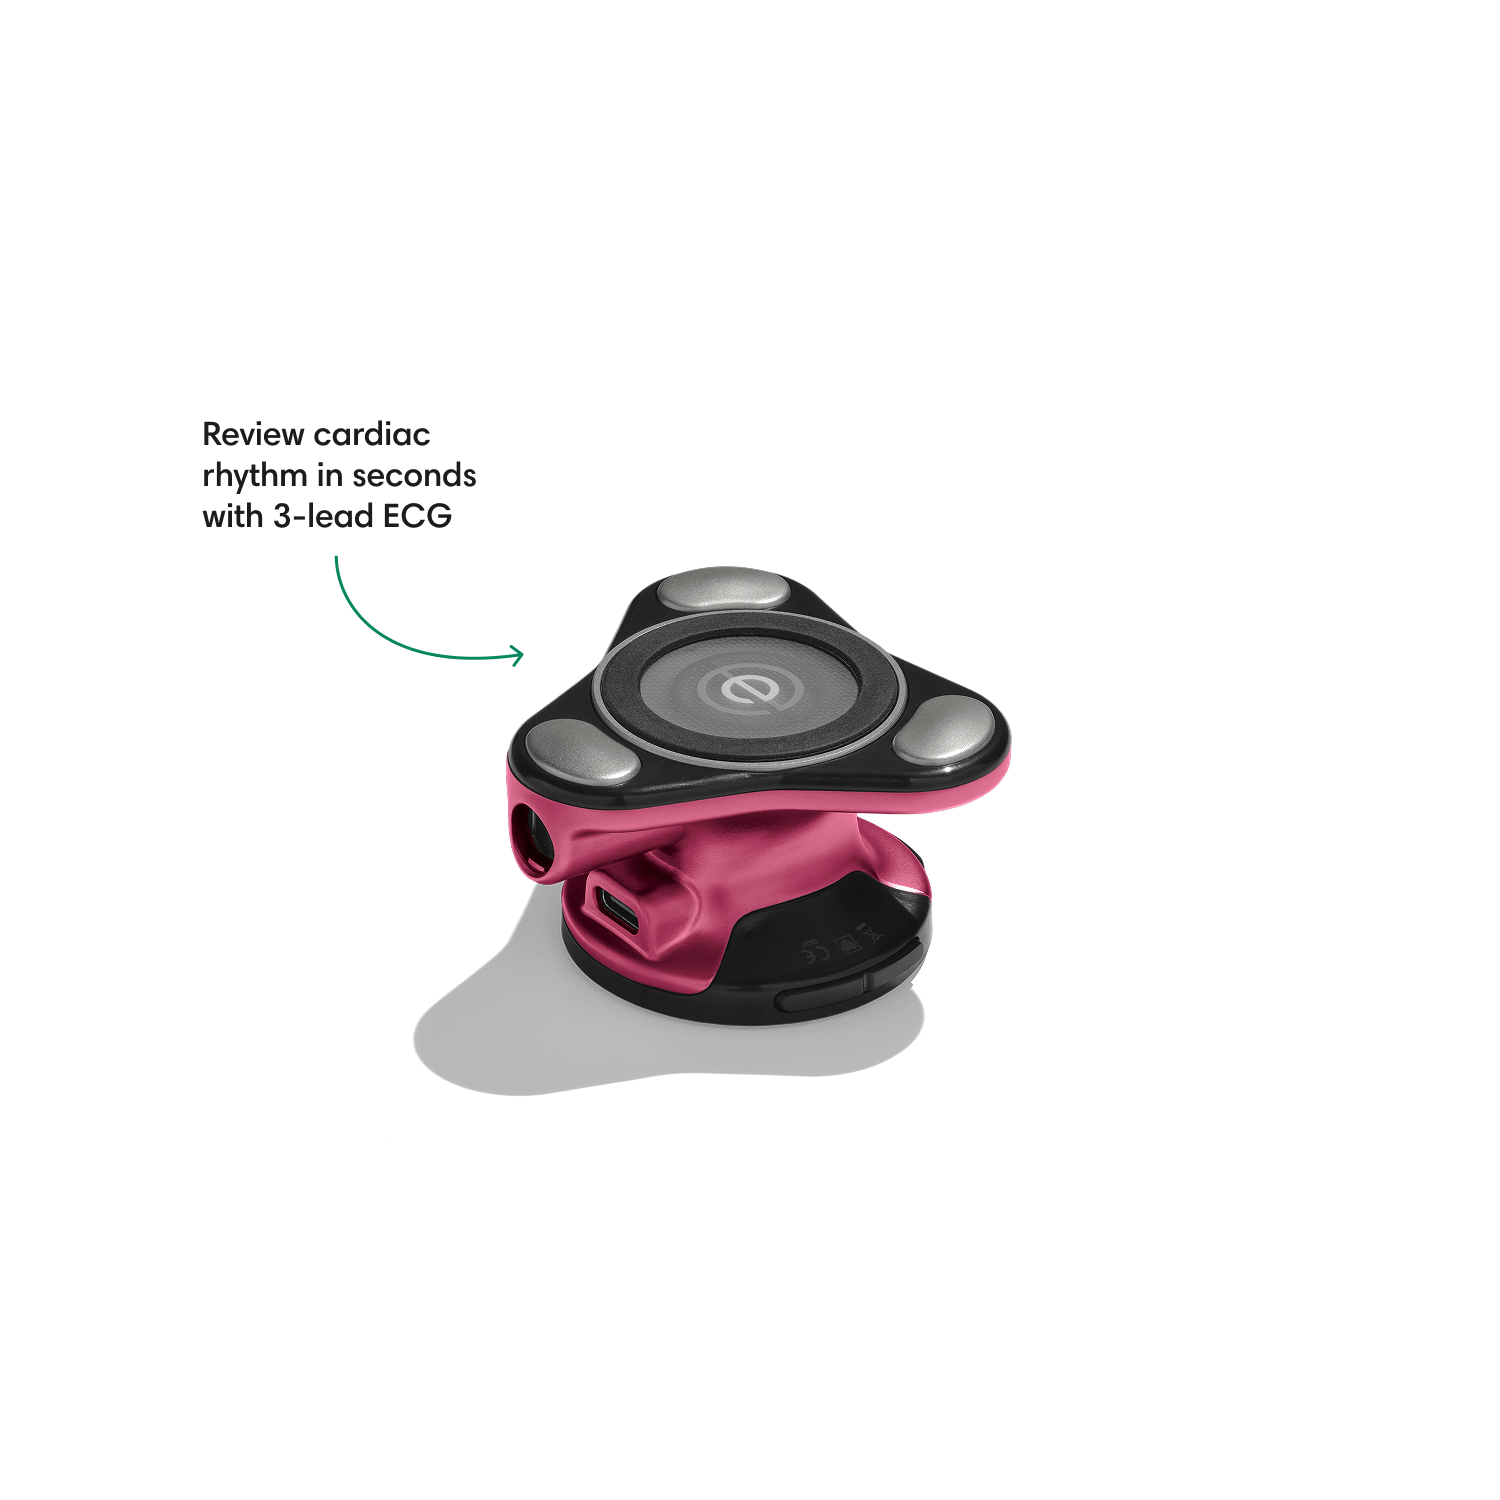

Go beyond sound alone.

For the first time ever, measure heart rate, visualize 3-lead ECG, and see detection results — right on a built-in, full-color display.